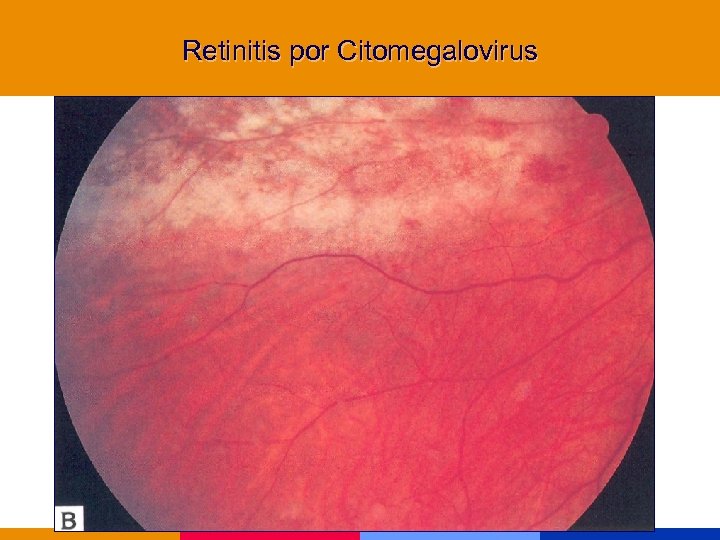

Retinitis por Citomegalovirus

Retinitis por Citomegalovirus

Retinitis por Citomegalovirus

Retinitis por Citomegalovirus

Retinitis por Citomegalovirus

Retinitis por Citomegalovirus

Retinitis por Citomegalovirus

Retinitis por Citomegalovirus